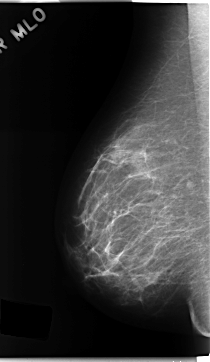

C_0161_1.RIGHT_MLO

RIGHT_MLO LINES 4704 PIXELS_PER_LINE 2728 BITS_PER_PIXEL 12 RESOLUTION 50 NON_OVERLAY